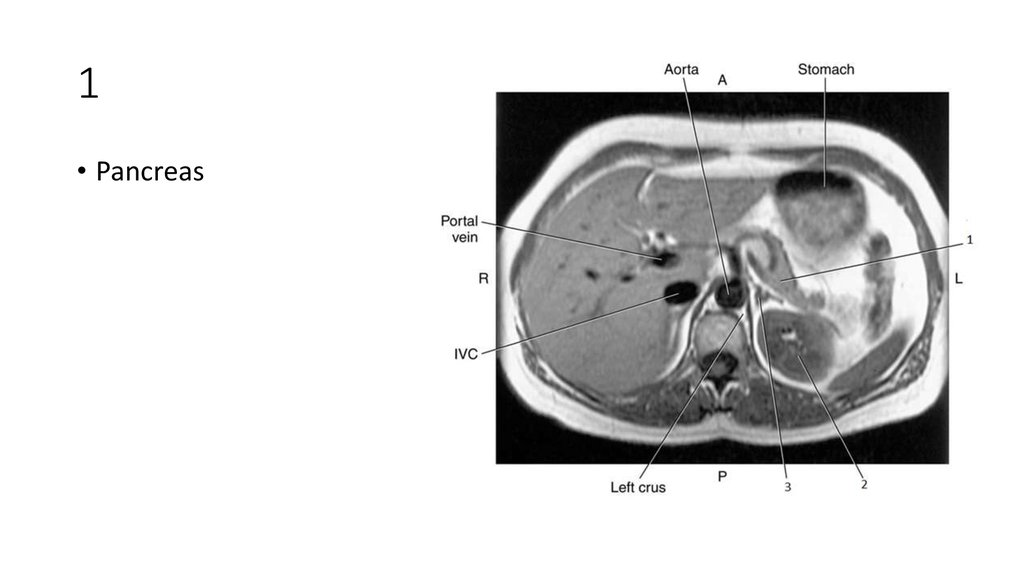

44. 1

45. 1

• Pancreas

46. 2

47. 2

• Left Kidney

48. 3

49. 3

• Left Adrenal Gland